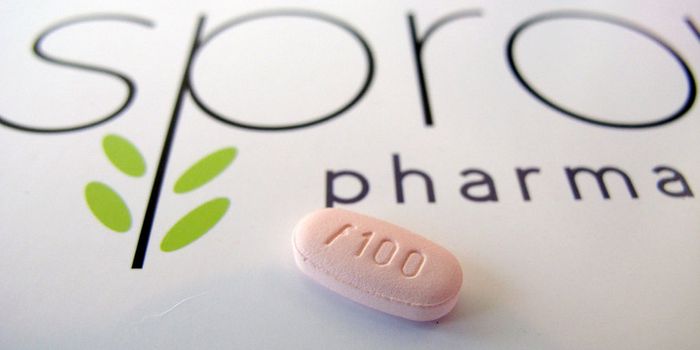

AUG 20, 2015Health & MedicineFor years, males with sexual problems looking for a solution have had many drug treatments to choose from. For the first ...